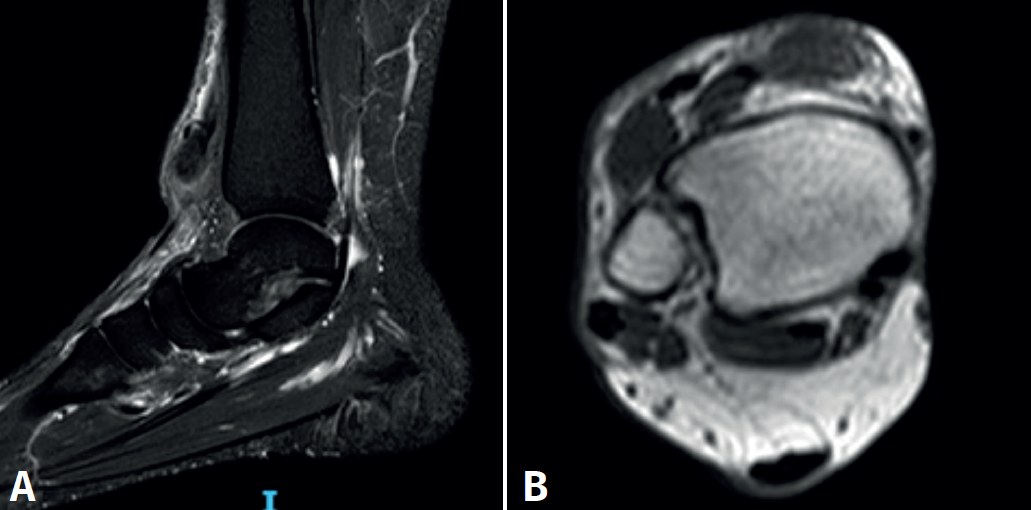

Se solicita ecografía, donde se corrobora rotura del tendón TA, por lo que se decide complementar con imágenes de resonancia magnética (RM), cuantificando una retracción de 65 mm sin otras lesiones asociadas (Figura 2).

Figura 2. Imágenes de resonancia magnética. A: sagital T2; B: axial T1. Rotura distal retraída del tendón tibial anterior.